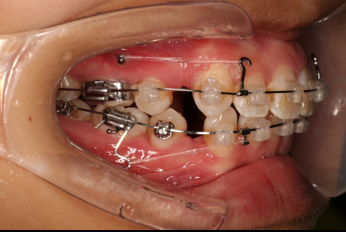

拔除14、24、34、44,上颌TPA+上颌高位支抗钉

2.第2.5个月:2017.1.13 ◆ 上颌加TPA,植入1312-08种植钉,上下0.16cu-niti

4.第6个月:2017.04.28 ◆ 上0.016*25ss 13/23v形曲,下0.017*25ss

5.第7个月:2017.05.26 ◆ 下颌36/46加power arm

6.第9个月:2017.07.25 ◆ 上前牙加颈部弹力线

7.第13.5个月:2017.12.15 ◆ 36/46远中倾斜,改变下颌牵引位置

2016.10.31  初戴,0.013cu-niti2017.1.13  上颌加TPA,U56间斜形植入韩国庆北1312-08种植钉,上下0.16cu-niti

2017.02.16  上下0.014*25 cu-niti,50g 拉尖牙远中

2017.04.28  上0.016*25ss 13、23近远中约5度 v形曲,下0.017*25ss

2017.05.26  磨牙近中倾斜,下颌36、46加power arm

2017.07.25  上前牙加颈部弹力线

2017.10.07  继续关间隙,下颌使用水平关间隙

下颌磨牙通过powerarm直立效果明显,下颌整平效果明显

2017.12.15  继续关间隙

2018.03.01上TPA加17、27颚侧牵引钩,压低17、27颚尖下颌43、32重粘,下颌0.016*25niti

2018.04.20  间隙基本关闭,上颌重新整平,精调

2018.5.25  (19个月)拆TPA,16、26粘tube 上颌0.14*25cu-niti  下颌0.018*25niti2018.7.23  上颌 0.017*25TMA,下颌0.017*25ss43压低曲,双侧后牙垂直牵引

2018.09.29  15、43、16、17、11、21重粘,上0.016*25cu-niti 下0.018niti 上连扎